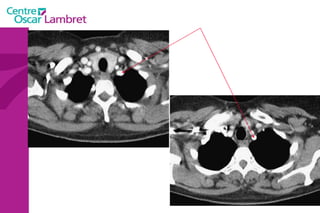

Les Troncs Supra Aortiques s’organisent autour de la trachée à leur origine. L’appareil circulatoire

Le  Tronc artériel Brachio-céphalique  : Naît de la face supérieure du 2e segment horizontal de la crosse aortique à hauteur de T 4. Volumineux, (diamètre 12 mm - longueur 3 cm) il se dirige en haut et à droite croisant la partie droite de la trachée. Derrière l’articulation sterno-claviculaire droite il bifurque en artères sous-clavière droite et carotide primitive droite.  L’appareil circulatoire

Les  artères Carotides Communes  : La droite vient du TABC. La gauche vient de la crosse de l’aorte. Elles n’ont aucune branche collatérale. L’appareil circulatoire

Artères sous-clavières  : l’une à droite et l’autre à gauche. La droite naît du tronc brachio-céphalique moins longue que la gauche, elle se dirige obliquement en haut et en dehors.  La sous-clavière gauche, au contraire, naît directement de l’aorte, remonte verticalement en haut. Arrivées au niveau de la première côte, ces deux artères présentent la même disposition, deviennent horizontales, passent entre les deux muscles scalènes et prennent le nom d'axillaires.

L’artère vertébrale  : Elle naît de la sous-clavière pré-scalénique et chemine verticalement sur 25 cm environ.  On lui décrit 4 segments. L’appareil circulatoire

L’artère mammaire interne  : naît de la face inférieure de la sous-clavière, un peu en dehors de la vertébrale. Elle épouse la partie antérieure du dôme pleural et descend verticalement à la face profonde du plastron costal à 1 ou 2 cm en dehors du bord latéral du sternum.  L’appareil circulatoire